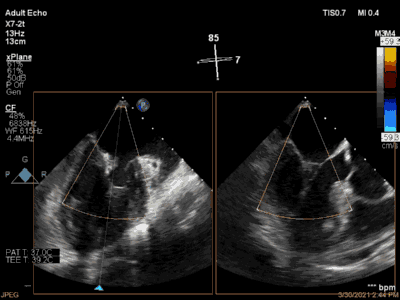

3月30日患者先在全麻下进行TEE(经食道超声心动图)再次评估瓣膜情况(视频4、视频5、视频6 ),确定为二尖瓣前组乳头肌断裂致二尖瓣前瓣脱垂并重度返流,其脱垂部位、瓣叶结构、瓣口面积等适合进行二尖瓣夹合术。术中IABP辅助,ECMO湿备,穿刺右侧股静脉,在TEE指导下顺利穿刺房间隔,随后送入二尖瓣夹合系统,在超声指导下于二尖瓣A2/P2区植入一枚Mitraclip XTR夹合器(视频7),术后TEE评估返流程度从5+降至1+(视频8 ),夹合结果满意,二尖瓣呈双孔启闭(视频9 ),术后二尖瓣平均跨瓣压差1mmHg(图1),收缩期肺静脉返流消失(图2 ),手术总耗时80min。香港亚洲医疗中心林逸贤教授通过视频连线进行手术全程技术支持。

图2